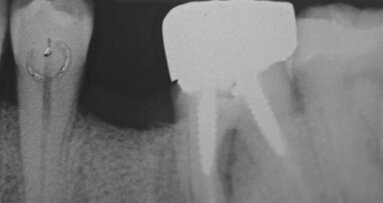

Le estrazioni sono state eseguite con tecnica chirurgica delicata tramite l’utilizzo di leve e pinze, senza eseguire osteotomia e senza danneggiare i tessuti perialveolari. Una volta estratto l’elemento dentario, all’interno dell’alveolo post-estrattivo è stato posizionato un blocchetto di Biopad®; per agevolarne la stabilizzazione è stato dato un punto a materassaio incrociato.

A 20 minuti dalle estrazioni è stata controllata la stabilizzazione del coagulo e i pazienti sono stati dimessi.

Nessuno dei dieci pazienti ha avuto complicanze emorragiche post-operatorie e a 7 giorni tutti i pazienti mostravano segni di epitelizzazione parziale, in 4 casi completa, degli alveoli post-estrattivi.

Nonostante si tratti di soli 10 casi clinici per un totale di 22 estrazioni e di uno studio osservazionale, il Biopad® si è dimostrato essere un buon presidio emostatico. Infatti, pur non avendo sospeso in nessun caso la terapia antiaggregante, non si sono verificate complicanze emorragiche o coaguli esuberanti al controllo.

Possiamo anche segnalare un buon effetto barriera esercitato dal materiale da innesto, che ha garantito un buon isolamento dei tessuti profondi fino alla formazione del tessuto di granulazione negli alveoli più grandi di dimensioni, come per i molari; pur evidenziando un ritardo di guarigione, abbiamo potuto rilevare come il collageno sia stato utile per la migrazione delle cellule epiteliali fino alla chiusura totale dei difetti senza mai manifestare alveoliti.